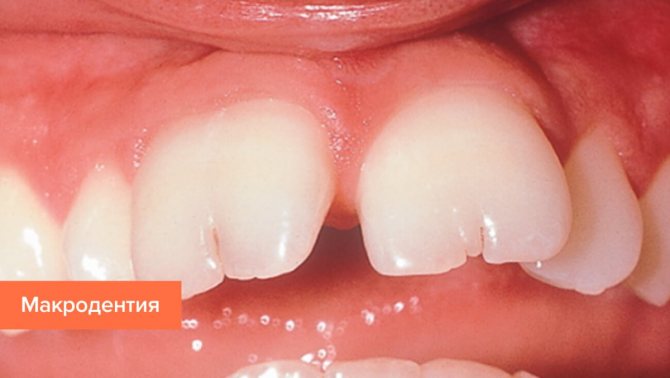

Макродентия характеризуется увеличенным размером коронковой части зубов. Этот тип отклонения гораздо опаснее для здоровья человека, чем микродентия. Состояние считается нормой только в том случае, если пациент имеет развитые челюстные структуры, в противном случае патология влечет за собой смещение единиц ряда и нарушение прикуса.

Стоматологи выделяют 2 вида макродентии: локализованную и генерализованную. При локализованном типе увеличено несколько элементов при генерализованной форме дефекта величина всех зубов превышает нормальные значения.

Макродентия – увеличенные зубы. Бывает у верхних резцов или боковых. Реже – на нижней челюсти, спереди. Превышение диагностируется при осмотре стоматологом, размеры его определяются при сравнении данных пациента со среднестатистическими. Оно может достигать диапазона 2–6 мм.

При диагностировании проверяют следующие размеры зуба: длину, ширину, высоту коронки. Ширина определяется измерением в самой широкой части зубного тела, высоту – от края десны пришеечной части до острого края или бугорка на жевательной поверхности. Макродентия на одной из челюстей вызывает диспропорции и нарушение прикуса.

Патологические размеры подразумевают слишком большие или слишком мелкие зубы. В первом случае налицо диагноз макродентия, который означает увеличенный размер коронки. Такая проблема приводит к трудностям с прорезыванием остальных «соседей», скученности и неправильному положению. Это косметическая патология, которая портит внешность. Лечение заключается в удалении и исправлении формы остальных зубов. Также проводится протезирование с целью закрытия дефектов.